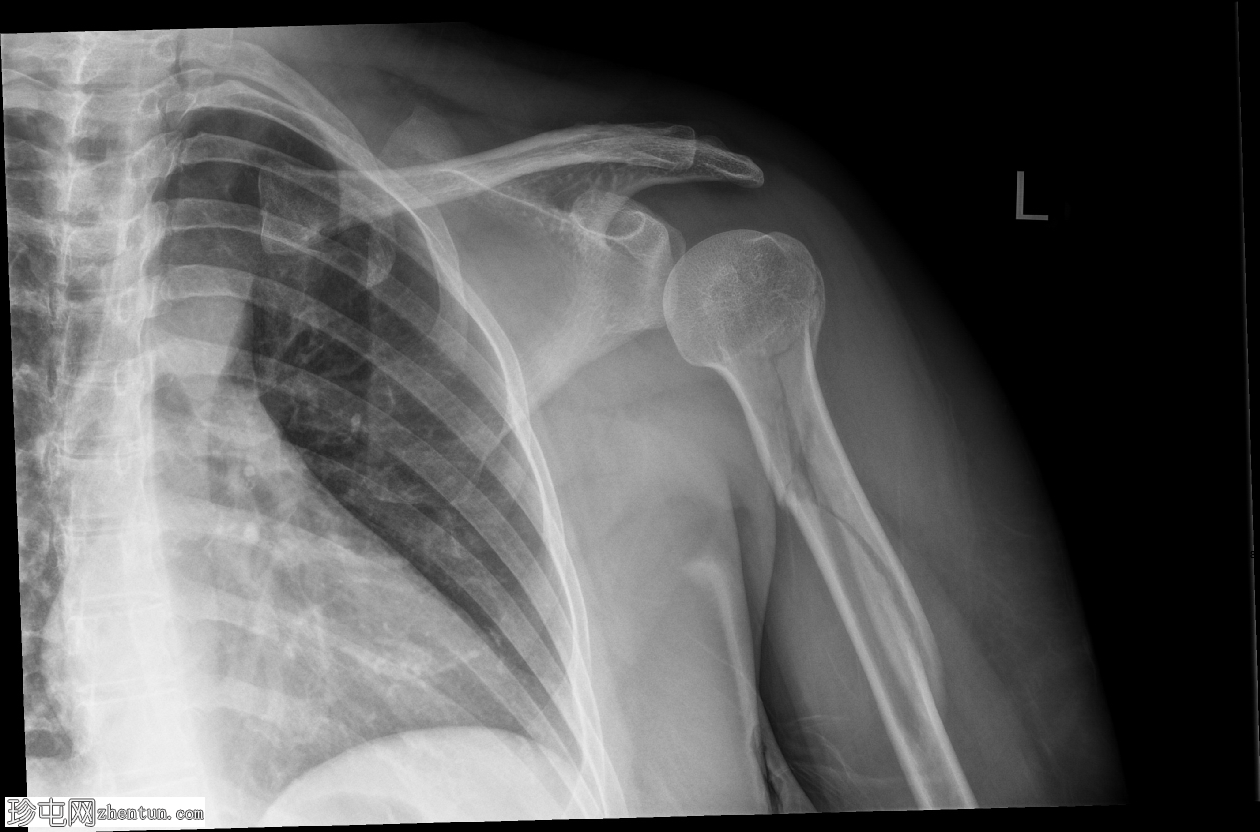

X线片

3.png

正位

肱骨近端粉碎性移位骨折,累及骨干近端半部、外科颈,并延伸至大结节。

肱骨头在肩关节内向下半脱位,肩峰肱骨间距增大。